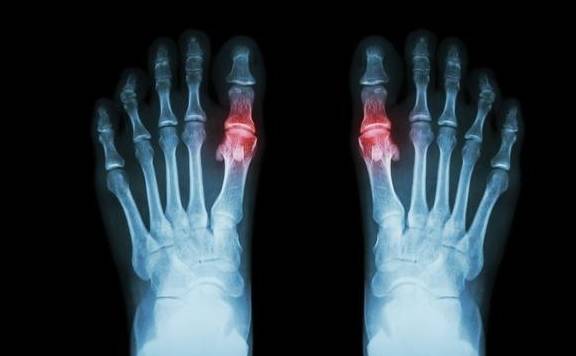

先是單關節,以第一趾關節居多,並逐步發展到足背、足跟、腳踝、膝、腕、和肘關節,部分患者可有發熱、寒戰、頭痛、心悸、惡心等全身癥狀,可伴有白細胞升高,紅細胞沉降等癥。

第三,痛風石病變期

癥狀:關節畸形,造成殘疾。

高尿酸血癥長期得不到有效的控制,慢慢會以結晶的形式沉積於皮下,關節滑膜、軟骨、骨質及周圍軟組織,形成痛風石。

皮下痛風石發生的典型部位是耳廓,關節周圍、跟骨和髕骨、滑膜等部位,皮下隆起大小不一的黃色贅生物,破潰後排出白色粉末或糊狀物。

痛風石可造成關節骨質破壞、關節周圍軟組織纖維化,引起常年的持續性關節腫痛、壓痛、畸形及功能障礙,造成殘疾。